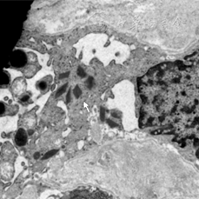

术后病理为(左)肾脏球旁细胞瘤,切面见囊实性肿物,大小1.5 cm×1.5 cm×0.8 cm,切面灰白、暗红色(图2)。免疫组化染色示CD34阳性,Vimentin弱阳性,CD7、CD10、EMA阴性;组织特染PAS阴性。肾组织各切缘未见肿瘤累及(图3)。电镜下胞质中可见菱形分泌颗粒,即不成熟的前肾素颗粒,具有诊断价值(图4)。